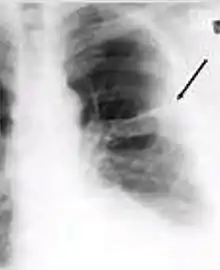

5. Hilar or mediastinal lymphadenopathy (bihilar lymphadenopathy) - Enlargement of lymph nodes in one or both hila or within the mediastinum, with or without associated atelectasis or consolidation.

Chest x-ray showing bilateral hilar adenopathy of primary pulmonary TB